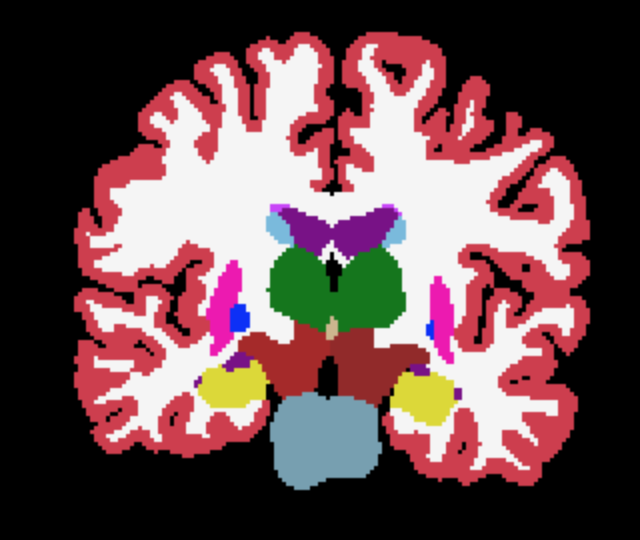

where and are the ground-truth and transformed segmentations respectively, and the Dice loss is now computed over multiple neuroanatomical structures (see Figure 1 for an example segmentation).

The overall training framework of the network is illustrated in Figure 1. Given an input scan, the network regresses both the coordinate means and the standard deviations , as well as a foreground mask . The optional atlas segmentation loss is denoted by the dashed box.

Third-level uncertainty: uncertainty at downstream tasks. To illustrate how the uncertainty could be used in a downstream task we show samples of atlas deformations and associated propagated segmentations in Figures 5 and 6. Both figures highlight the variability of the samples, which would have a direct effect on any downstream analysis using quantities extracted from the segmentations, e.g., regional volume (Desikan et al., 2009). The sample-to-sample differences, along with the variance, are again concentrated on the cortex. This registration-based uncertainty, when not accounted for, can decrease the power of downstream statistical analyses, or be mistaken for aging effects if the registration errors correlate with age.